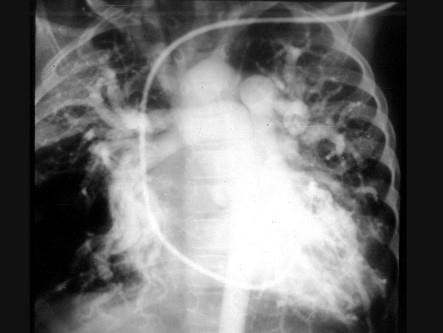

问题 5岁患儿,生后3个月发现心脏杂音。曾患4次肺炎。胸骨左缘34肋间闻及4/6级全收缩期杂音,心尖区有短促的舒张期杂音。右心导管检查如图,导管可从右室进入左室,右室血氧高于右房。可能的诊断是 ( )

选项 A、风湿性二尖瓣狭窄 B、肺动脉狭窄 C、室间隔缺损 D、动脉导管未闭 E、房间隔缺损

答案 C